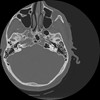

7 HUESO,,Vol,0.5,HUESO,,